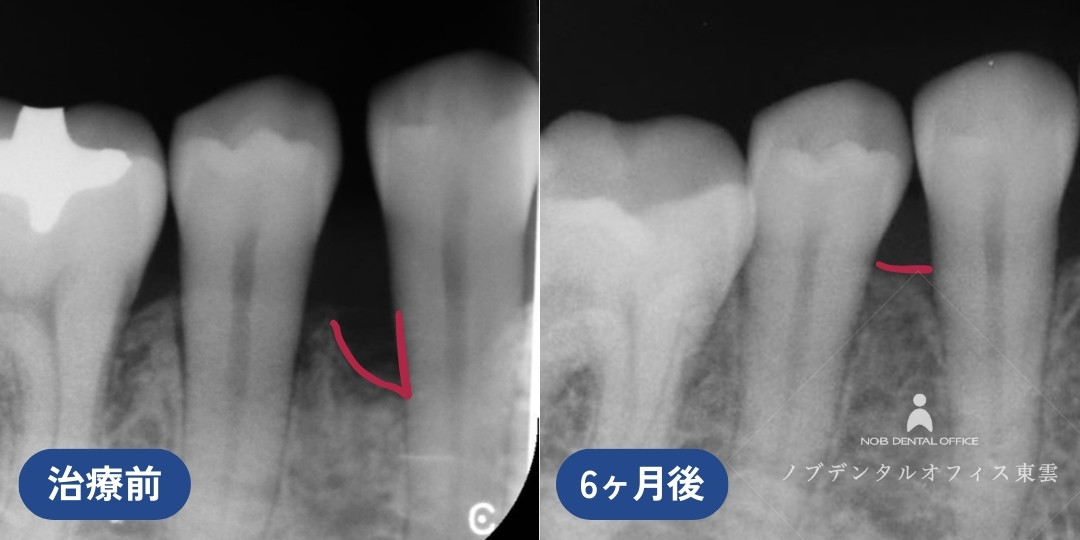

中等度歯周病を保険診療で再生治療した症例(40代女性)

歯周病の治療をしたいと来院されました。

歯周基本治療を行い、保険適用のリグロスを用いた歯周組織再生療法を行いました。

リグロスを用いた歯周組織再生療法後、骨の再生が認められました。※写真内赤線箇所

診断の結果、レントゲンが黒くなっている部分があり、骨が吸収されていました。中等度の歯周病です。

歯周基本治療を行い、歯周組織再生療法を行いました。

BEFORE

レントゲンの赤線箇所の骨が溶けています。

AFTER

再生療法6ヶ月後、赤線箇所の骨の回復が確認されました。